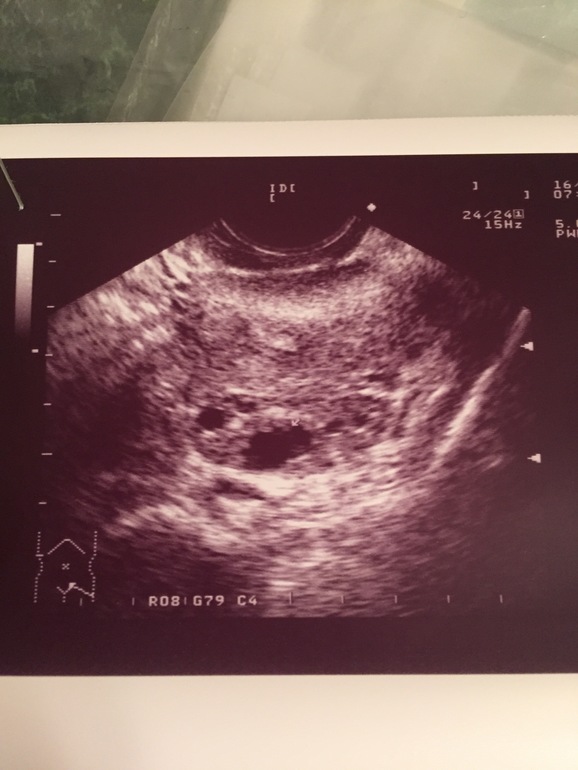

Второй снимок точно ЖТ - моя узистка так м говорит - видишь образование похожее на звездочку, знай - ЖТ.

Я бы сказала так, на первом выглядит как дф, на втором как жт. Странно

тоже вижу жт на втором.

На втором снимке жт,края неровные